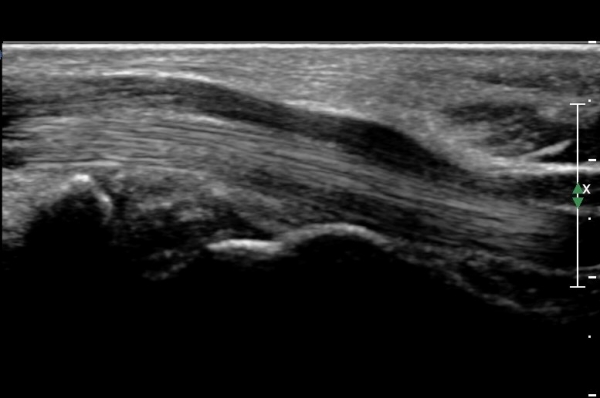

¼ö±Ù°ü ±ÙÀ§ºÎ(scaphoid, lunate level)¿¡¼ Á¤Á߽Űæ Ⱦ´Ü¸é°Ë»ç»ó Á¤Á߽ŰæÀÇ Àú¿¡ÄÚ ºÎÁ¾ÀÌ °üÂûµÊ.(»çÁø 2).